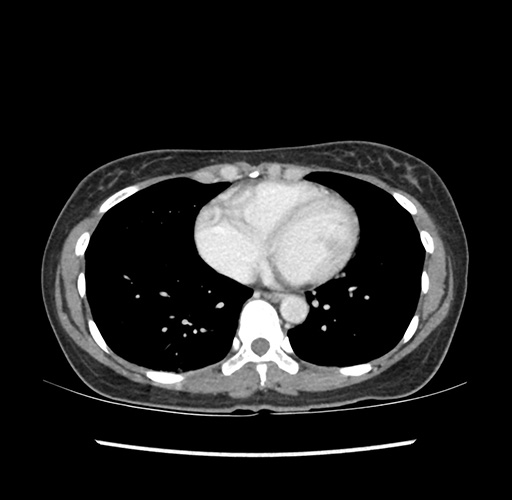

Imaging Analysis

Look through the patient's CT scan to identify any areas of concern for the necessary procedure.

Based on your CT findings, which issue(s) would give reason for "planned slowing down moment(s)" in this case?